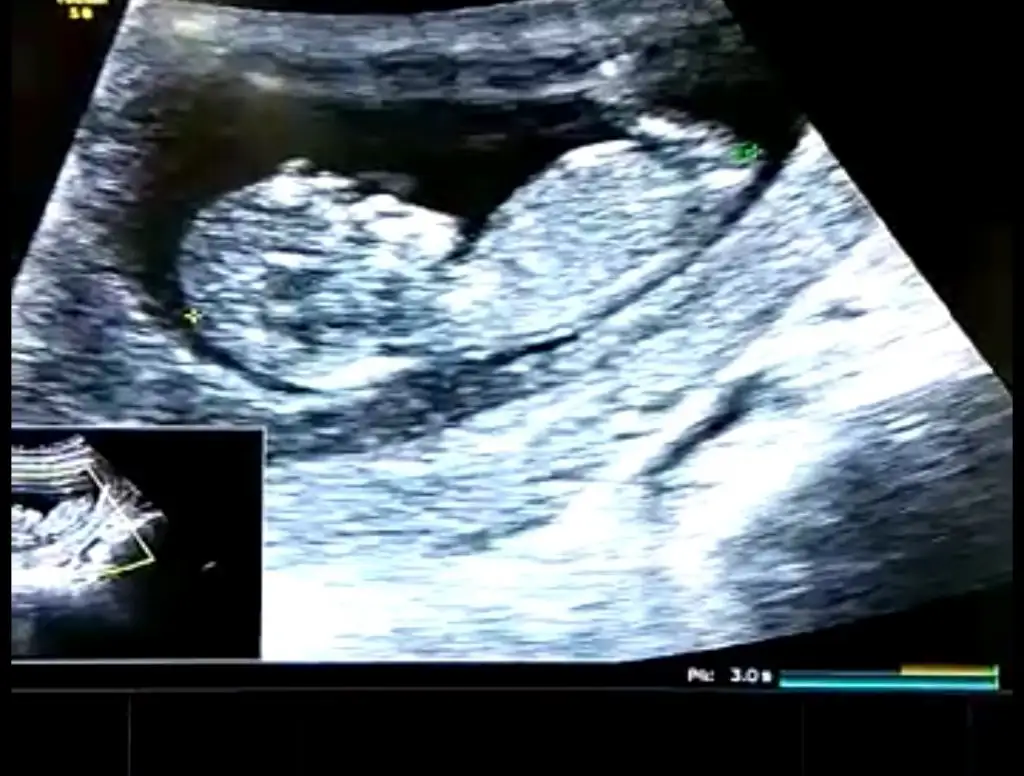

Karından bakıldı ise kız en iyi nub için 11 12 13 hafta paylaşınIkra meyra canım bakar mısın ilk fotoyu atmıstım daha önce ikinci foto 7. Haftadan

Canım ilk foto için karındansa erkek demiştin bende 7. Hafta fotosunu atayım dedim 10. Haftamda tekrar gideceğim o zaman yine atayımKarından bakıldı ise kız en iyi nub için 11 12 13 hafta paylaşın

Evet biliyorum ilkte erkrek demiştim kese konumu pek guven vermiyor o nedenle 11 12 13 hafta usg olursa paylalın 10 haftada değilde 11 haftada gitsenizCanım ilk foto için karındansa erkek demiştin bende 7. Hafta fotosunu atayım dedim 10. Haftamda tekrar gideceğim o zaman yine atayım

Mrb 13 haftalik olduk cok sukurKız gibi net de değil kız sanki 12-13 olunca tekrar usg paylaşın